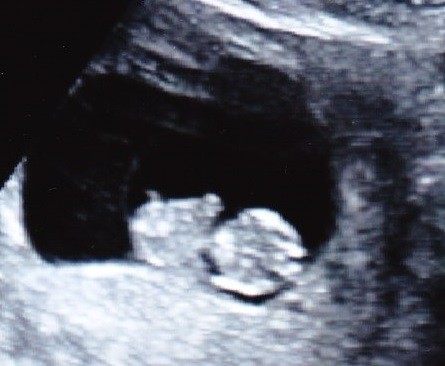

Widziałam malucha, oczywiscie serca bijącego znowu nie zobaczylam od razu

Usg swietne, nie zaluje ani grosza. Byłam z mezem i mala. Super warunki, ja sobie leze, oni wygodnie siedza obok a przed nami wielki tv z fasolka. Posprawdzala babeczka jajniki, macice i wsio co mozna, zadnych problemow, zadnych krwawien czy innych wyciekow w srodku, na jajnikach nie ma torbieli. Serce pieknie bije, pokazala mi przeplyw na sercu i pepowinie, wszystko idealne. Od wtorku fasol wiekszy i dzis juz mial 25,1mm. Termin potwierdzony na 05.08.

Mam zdjecia, wkleje zaraz. w tym jedno z wtorku.